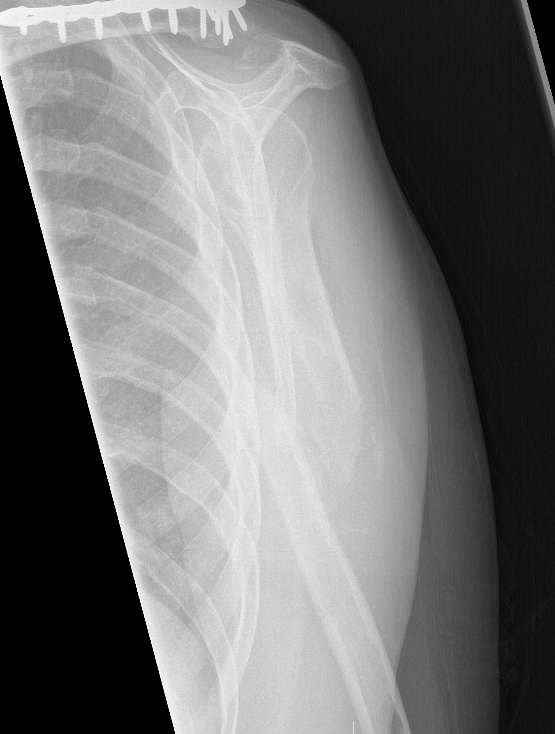

Prox humerus 1Prox humerus 2Prox humerus ORIFProximal humerus ORIF

Proximal third humerus ORIF of nonunion